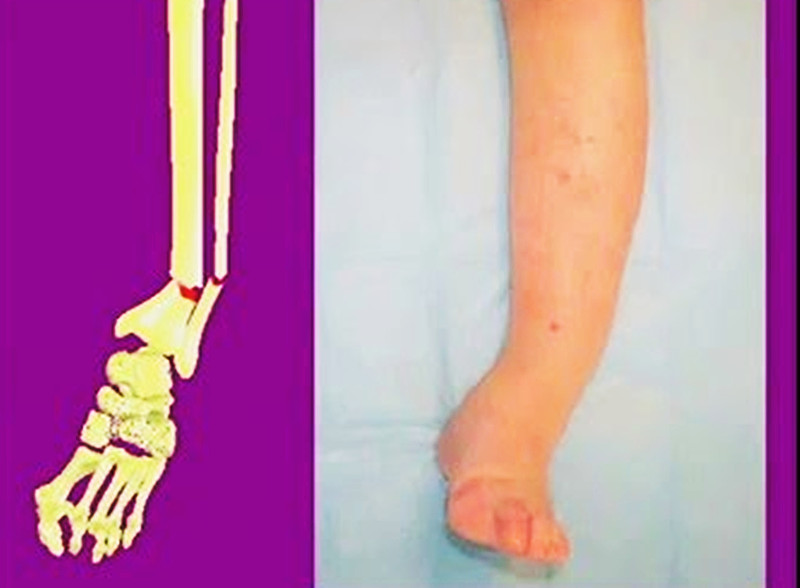

下图第一张图片显示一位患者的骨不连骨折手臂,第二张图片显示已治愈。